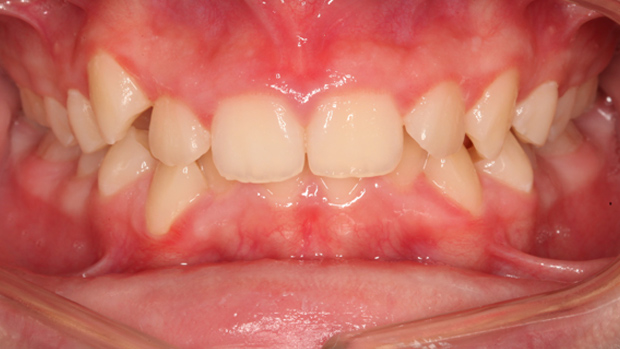

Причина обращения пациента: скученность зубов, выпирающие резцы, начавшаяся патологическая стираемость нижних зубов

Папа привел В. на консультацию с типичной жалобой на неровные, скученные и выпирающие вперёд зубы. Однако внимательный осмотр выявил куда более серьёзную проблему: на резцах нижней челюсти уже были заметны признаки патологической стираемости эмали.

Почему это произошло у ребёнка? Причина часто кроется в неправильном прикусе. Диагноз В. – выраженная скученность. Когда зубам тесно, они занимают неправильные позиции, и некоторые из них (чаще всего выступающие вперёд нижние резцы) начинают принимать на себя более сильную нагрузку, для которой не предназначены. Иногда к этому добавляются и психологические факторы, усугубляющие проблему.